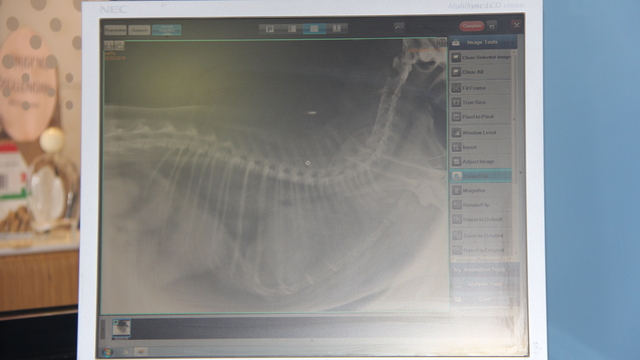

Klinikte kullanılan bir örneği paylaşan Özmen, "Solunum problemi olan bir hastamız vardı. Bu hastamızın toraks dediğimiz göğüs boşluğunda sıvı birikmesi vardı. Biz buradaki sıvı birikmesinin nedenlerini tabii ki araştırdık ama aynı zamanda da gözümüzden kaçan ekstra bir şey var mı diye, yapay zeka teknolojisine bunu yükledik. Kendisine sorularımızı yönelttik. Hastanın durumunu, anamnezinden bahsettik. Bu bilgileri vermezseniz o da çok fazla seçenek sunabiliyor. Siz seçenekleri daralttığınız zaman daha fazla yardımcı olabiliyor. Sonuçta o da bizimle mutabık kaldı. Teşhisimizi check etmiş olduk. Hastaya da o şekilde tedavimizi uyguladık" dedi.